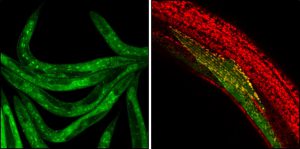

Τίτλος Ερευνητικού Έργου: Ενισχύοντας τις ευεργετικές ιδιότητες των ΚΝΣ μακροφάγων για την προαγωγή της επαναμυελίνωσης, ως μια πρωτότυπη θεραπευτική στρατηγική για την προϊούσα Πολλαπλή Σκλήρυνση

Επιστημονική Υπεύθυνη: Probert Lesley